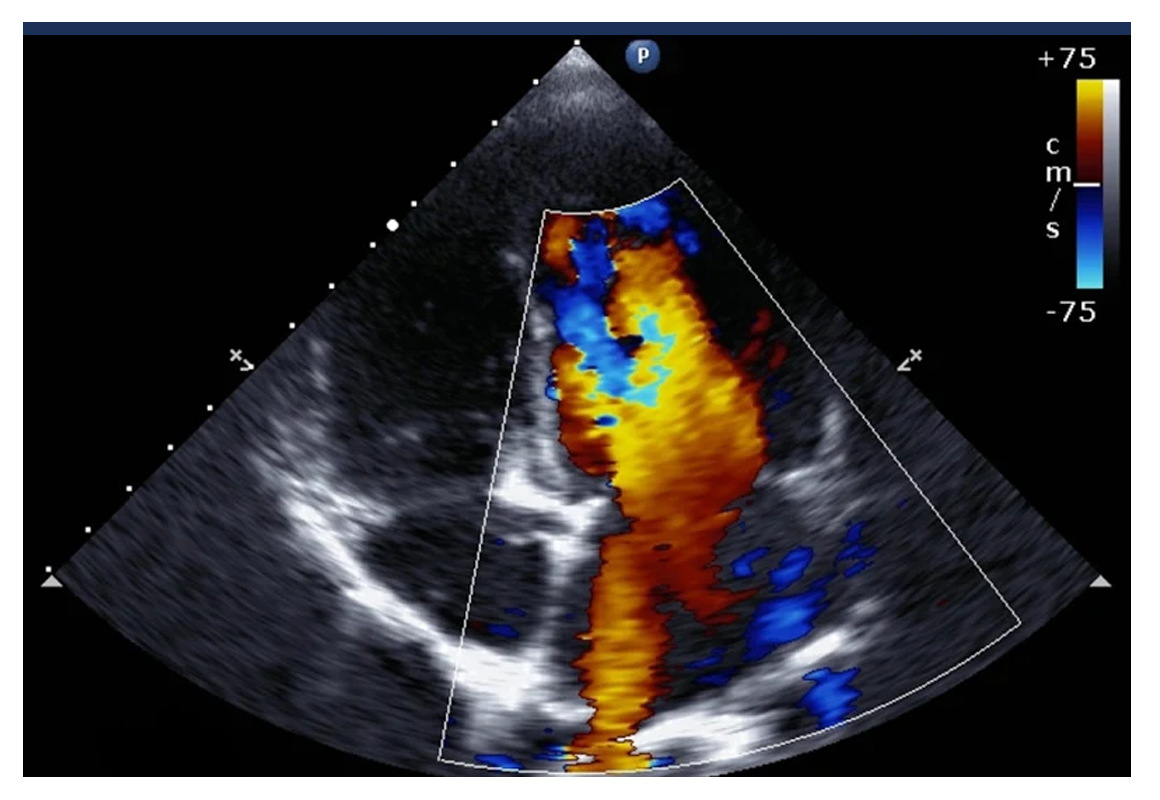

Although you won't be able to feel anything during the echocardiogram test, the probe will be sending out ultrasound waves and creating an image of your heart from the echoes that bounce back. A constantly updated image will be displayed on the monitor, allowing your doctor to examine the structure and function of your heart.

Your doctor will be looking for any abnormalities in the size or shape of your heart and assessing how well it is pumping. Together with information gathered from ECGs and other tests, the echocardiogram could help your cardiologist diagnose problems such as a heart valve disorder or coronary artery disease. An ecg test could also be used to check for fluid around your heart or to monitor your recovery after a heart attack.